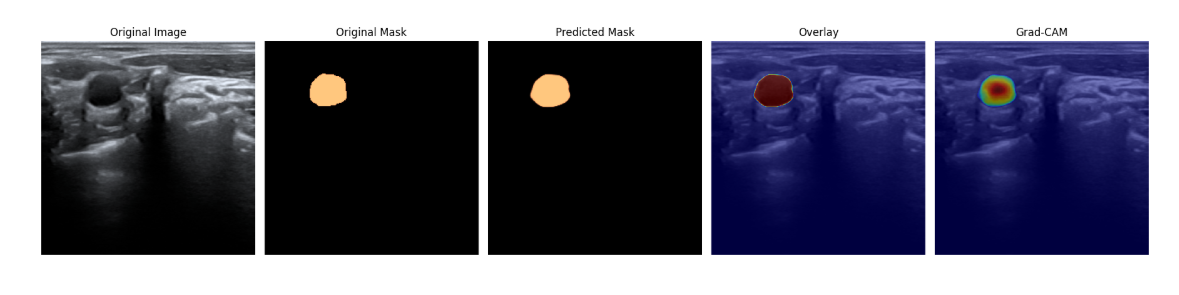

预测的部分结果展示:

- 颈动脉分割 :通过对颈动脉的分割,可以更清晰地观察和分析颈动脉的结构和病变情况,为疾病的诊断和治疗提供依据。

- 颈动脉几何形状测量和评估 :借助该数据集,研究人员可以开发和测试各种算法,以精确测量颈动脉的几何形状,为心血管健康评估提供量化指标。

- 计算机视觉算法的开发和测试 :为计算机视觉领域的研究人员提供了丰富的数据资源,可用于训练和优化各种算法模型,提高算法在医学影像分析方面的性能和准确性。